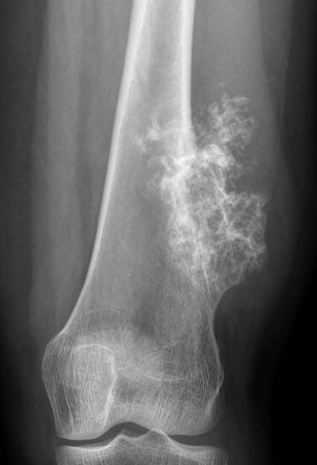

Malignant Transformation

Low-grade chondrosarcoma

- isolated lesion < 1%

- more common with central lesions

Suspicious features

- growth after maturity

- increased thickness of cartilage cap on CT / MRI - > 2 cm

- increasing pain

- increased calcification / bony erosion / lytic areas on xray

- septal enhancement after MRI with gadolinium

- MRI / CT of 64 benign osteochondromas and 34 secondary chondrosarcomas

- cartilage cap 2 cm or more 100% sensitive and 98% specific for secondary chondrosarcoma